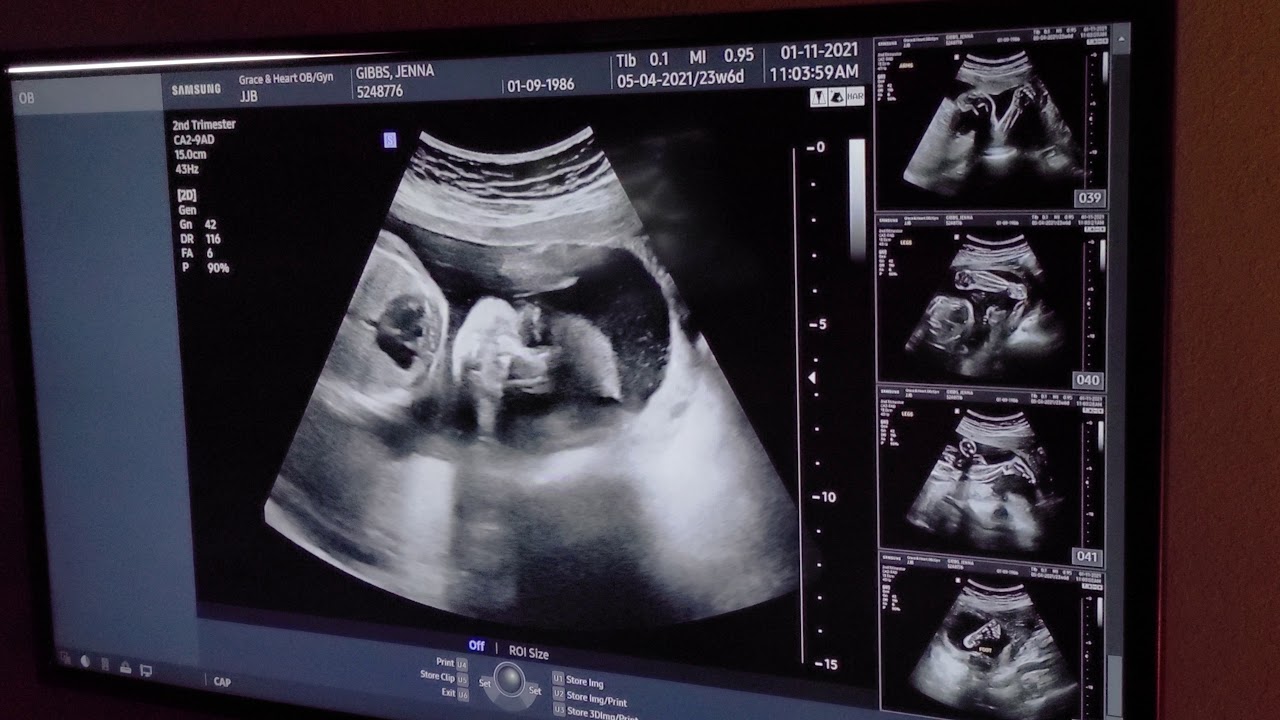

Print The girl ultrasound gallery is designed to show you what a baby girl looks like on ultrasound photos from various weeks of pregnancy You'll notice that what you see varies a lot by the number of weeks of gestation Each week in pregnancy can look slightly different This can be due to the baby's development, the weight of the mother It's not likely you'll get an ultrasound at 25 weeks pregnant, unless your doctor has ordered extra monitoring for baby You'll see the OB once this month if you haven't already Starting at week 28, your visits will be every two weeks The glucose screening test will happen between weeks 24 and 28#35weeks#8monthspregnant#Baby boy This video ultrasound was given to us by my hospital and happily sharing with you guys Thank you for all your support Lo

All that and potential symptoms listed on Raising Tot website A 24 weeks pregnant ultrasound would show they're gaining weight, moving, and have recognizable faces The position of your babies at 24 weeks may still be changing as they might have a little room to move around Single babies settle into position in the last weeks of pregnancy, but twins will run out of room to move sooner LungsThis is usually done between 18 to 24 weeks, which is the second trimester of the pregnancy Takeaway Many myths revolve around the prediction of the baby's gender such as the information from the heart rate But babies' heartbeat changes throughout the pregnancy and a normal fetus beat at the same average rate, be it a boy or girl

Pregnancy week 24 fetal development At 24 weeks, your baby has developed all body parts, including their face Their skin is reddish and wrinkled, and because of a lack of underlying connective tissue, their skin is also thin and translucent Depending on your body type, your bump may be subtle or more prominent The 12week ultrasound is usually an external scan (In occasional cases, an internal — known as transvaginal — scan may be necessary if the external scan can't produce aAt 24 weeks I had my anatomy scan Communities > Pregnancy Ages 2534 > ultrasound at 24 weeks A A A Close Pregnancy Ages 2534 Community 256k Members I'm 33 weeks with my second baby Early on, I had the genetic blood test done for risk assessment purposes

What you can expect to see During the 16week scan, you can expect to see a baby that is fully formed but just very small But, if their development is on A midpregnancy (anatomy) ultrasound takes longer – about to 45 minutes – because the sonographer will look closely at your baby's basic anatomy, including the head, brain, face, neck, chest, heart, spine, stomach, kidneys, bladder, arms, legs, and umbilical cord so your provider can make sure they're developing properly 24 weeks pregnant ultrasound boyBaby development at 24 weeks Getting ready to breathe Respiratory sacs at the tips of the smallest branches of your baby's lungs are growing and multiplying, adding more surface area for the exchange of oxygen and carbon dioxide once your baby is born Still skinny, but not for longPicture of Second Trimester (24 Weeks) Second

24 Weeks Pregnant Ultrasound It S A Boy Youtube